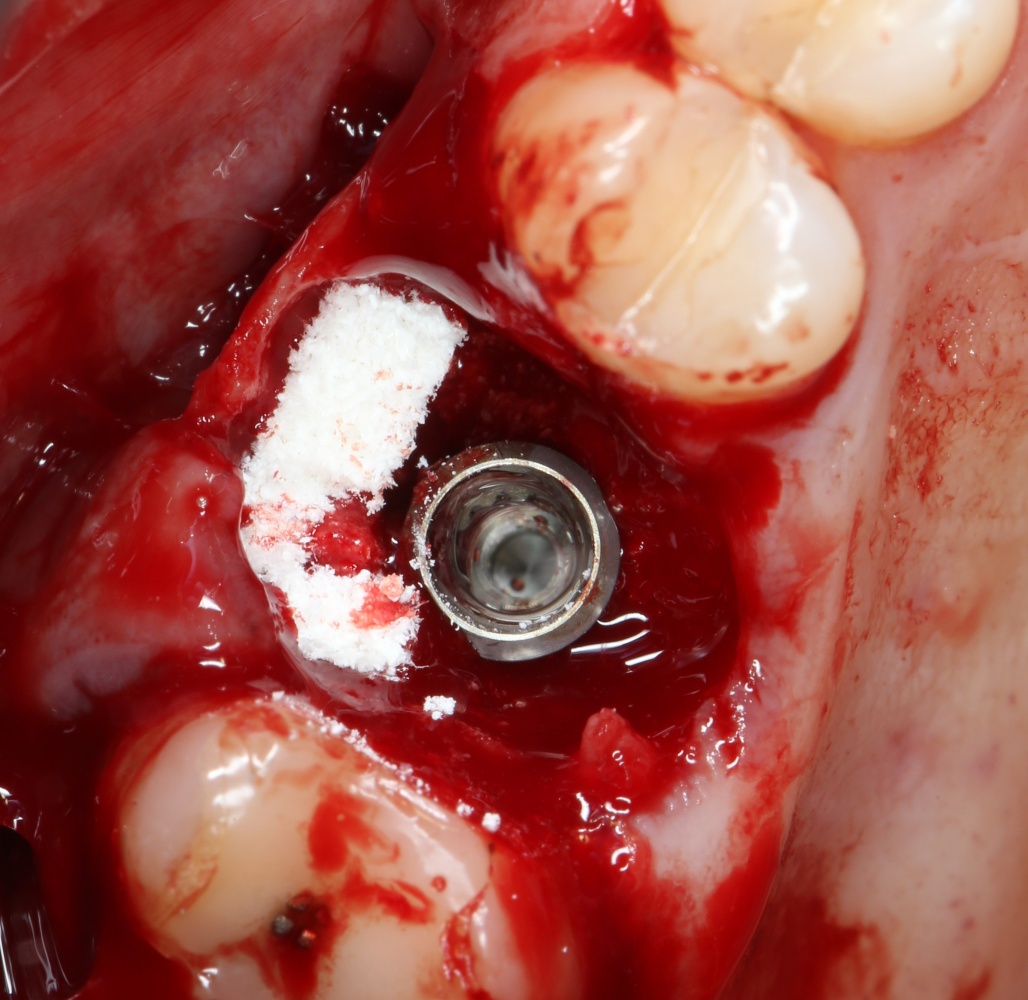

Устанавливается имплантат Astratech (Dentsply Implants):

Для аугментации также используем Bio-Oss Collagen 100 mg, нарезаем его по размеру с помощью скальпеля и позиционируем в лунках щечных корней:

На имплантат ставим формирователь, ушиваем лунку. Напомню, что любой биоматериал должен быть герметично запечатан в ране (фактор успеха III). В противном случае, от него больше вреда, чем пользы:

Совсем уж стягивать края раны не нужно (если бы мы использовали обычный Bio-Oss, то это было бы необходимо). Отличие Bio-Oss Collagen еще и в том, что он не размывается при кровотечении.